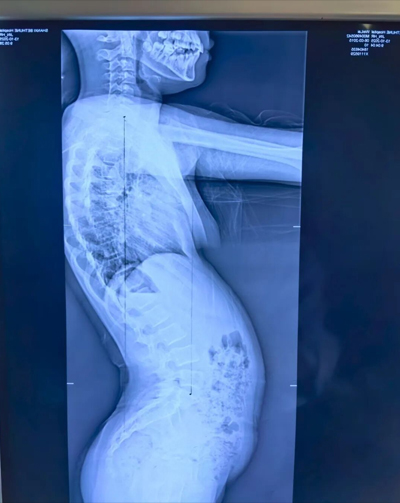

在门诊接诊的青少年中,“懒骨头体态” 最为普遍 —— 孩子总是含胸驼背、头向前探,腰椎看似放松却总也直不起来,整体姿势像一个软塌塌的 “问号”。家长们往往以为是孩子缺乏自律、不爱挺拔,但其实这是身体的 “被动选择”,本质是身体在 “挪出空间” 保护内脏,而非主动偷懒!

更值得警惕的是,这种 “懒骨头体态” 还会与脊柱侧弯相互影响:消化异常导致体态失衡,失衡的体态又会加重脊柱侧弯的进展,形成 “消化差→体态糟→侧弯重” 的恶性循环,不仅影响孩子的外形气质,还可能引发腰酸、腹胀、注意力不集中等问题。